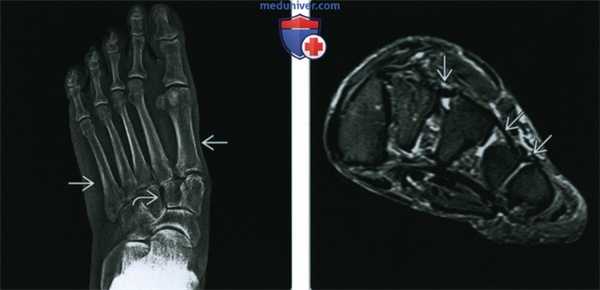

(Слева) Рентгенография в ПЗ проекции: плоская стопа, обусловленная болезнью Марфана. Наблюдается пронация переднего отдела стопы, определяемая по отклонению оснований плюсневых костей. Также имеется просвет между клиновидными костями, что говорит об ослаблении связок.

(Справа) МРТ Т2ВИ, режим подавления сигнала от жира, корональный срез: у этого же пациента определяется растяжение межклиновидных и межплюсневых связок В, что приводит к аномальному просвету между клиновидными и плюсневыми костями. На других изображениях (не представлены) определялись разрывы сухожилий, все это вносит вклад в формирование клинически плоской стопы, характерной для болезни Марфана.